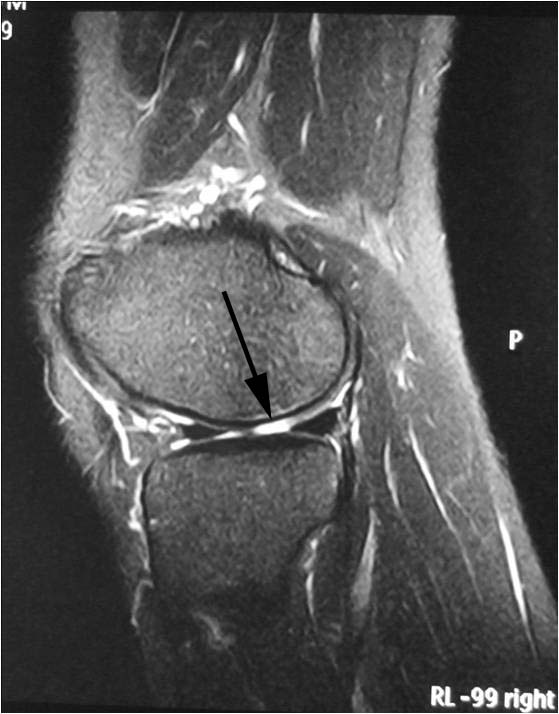

Sure. This is a person who has pain in the right knee after when playing tennis. MRI scan showed a full thickness cartilage defect (or torn cartilage) in the lateral (outer) femoral condyle.

This is how it looks like during arthroscopy: